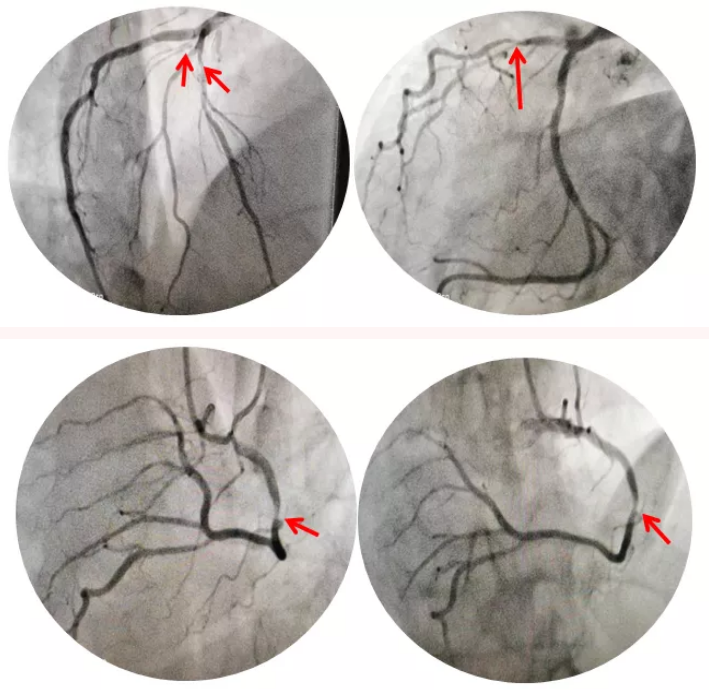

图一:患者造影图像

此次接受手术的吕大叔是一位59岁的中老年患者,因反复胸闷胸痛1月余,遂就诊于北京燕化医院,门诊心脏CTA提示前降支、右冠状动脉重度狭窄。患者入院后考虑到患者心脏位置和正常人相反,行冠脉造影时需充分利用镜像原理,投射体位和操作手法均与正常左位心相反,这无形中增加了手术的难度和风险。

准备就绪后,在北京阜外医院专家指导下,我科李钢主任和王志勇副主任医师上台迅速完成造影,发现患者前降支狭窄80%,对角支狭窄80%,右冠状动脉狭窄90%,征得患者同意后,在OCT指导下给予患者右冠状动脉植入支架一枚。经过一个小时的手术时间,成功完成了这台非比寻常的冠脉支架植入术。